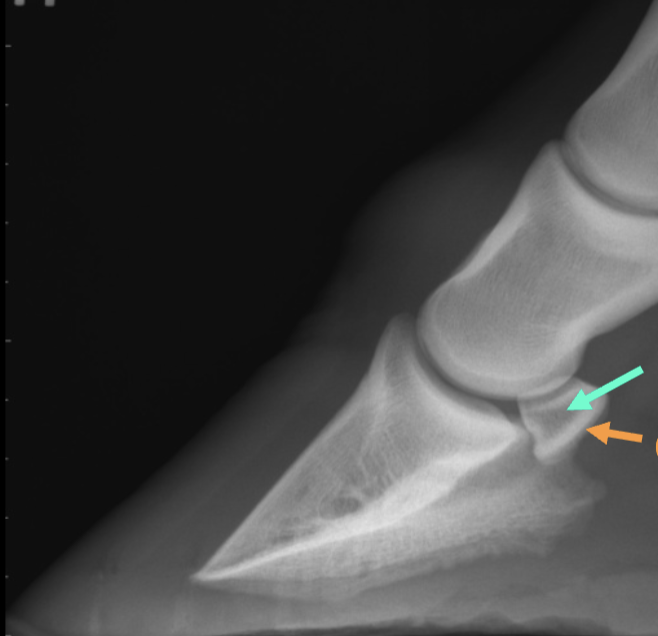

what is the teal arrow

medullary cavity

what is the orange arrow

cortex